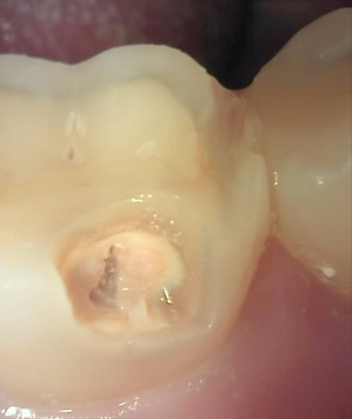

Before

육안으로는 잘 식별하기 어려운 치아 우식을

큐레이로 촬영해보면 붉은색으로 쉽게 발견할 수 있습니다.